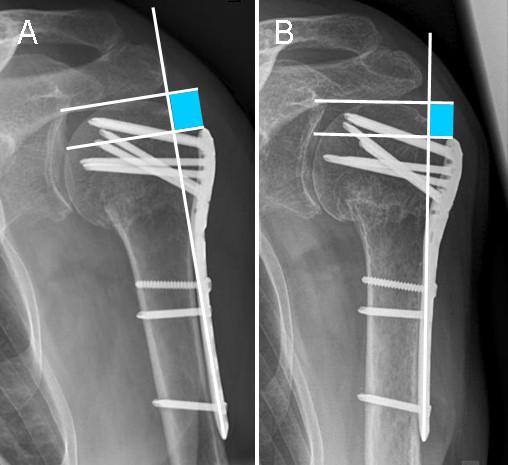

Patients with a proximal humeral fracture who underwent angular stable plate fixation between 01/2007 and 07/2009 were included. On AP views of the shoulder, the difference in height between humeral head and the proximal end of the plate were determined postoperatively and at follow-up. Additionally, the occurrence of complications was documented. Patients with calcar screws were assigned to group C+, patients without to group C-.

方法

纳入 2007 年 1 月至 2009 年 7 月期间接受角稳定钢板固定术治疗肱骨近端骨折的患者。术后和随访时,在肩关节正位 X 线片上测量肱骨头和钢板近端之间的高度差异。同时记录并发症的发生情况。有骺板螺钉的患者分为 C+组,无骺板螺钉的患者分为 C-组。